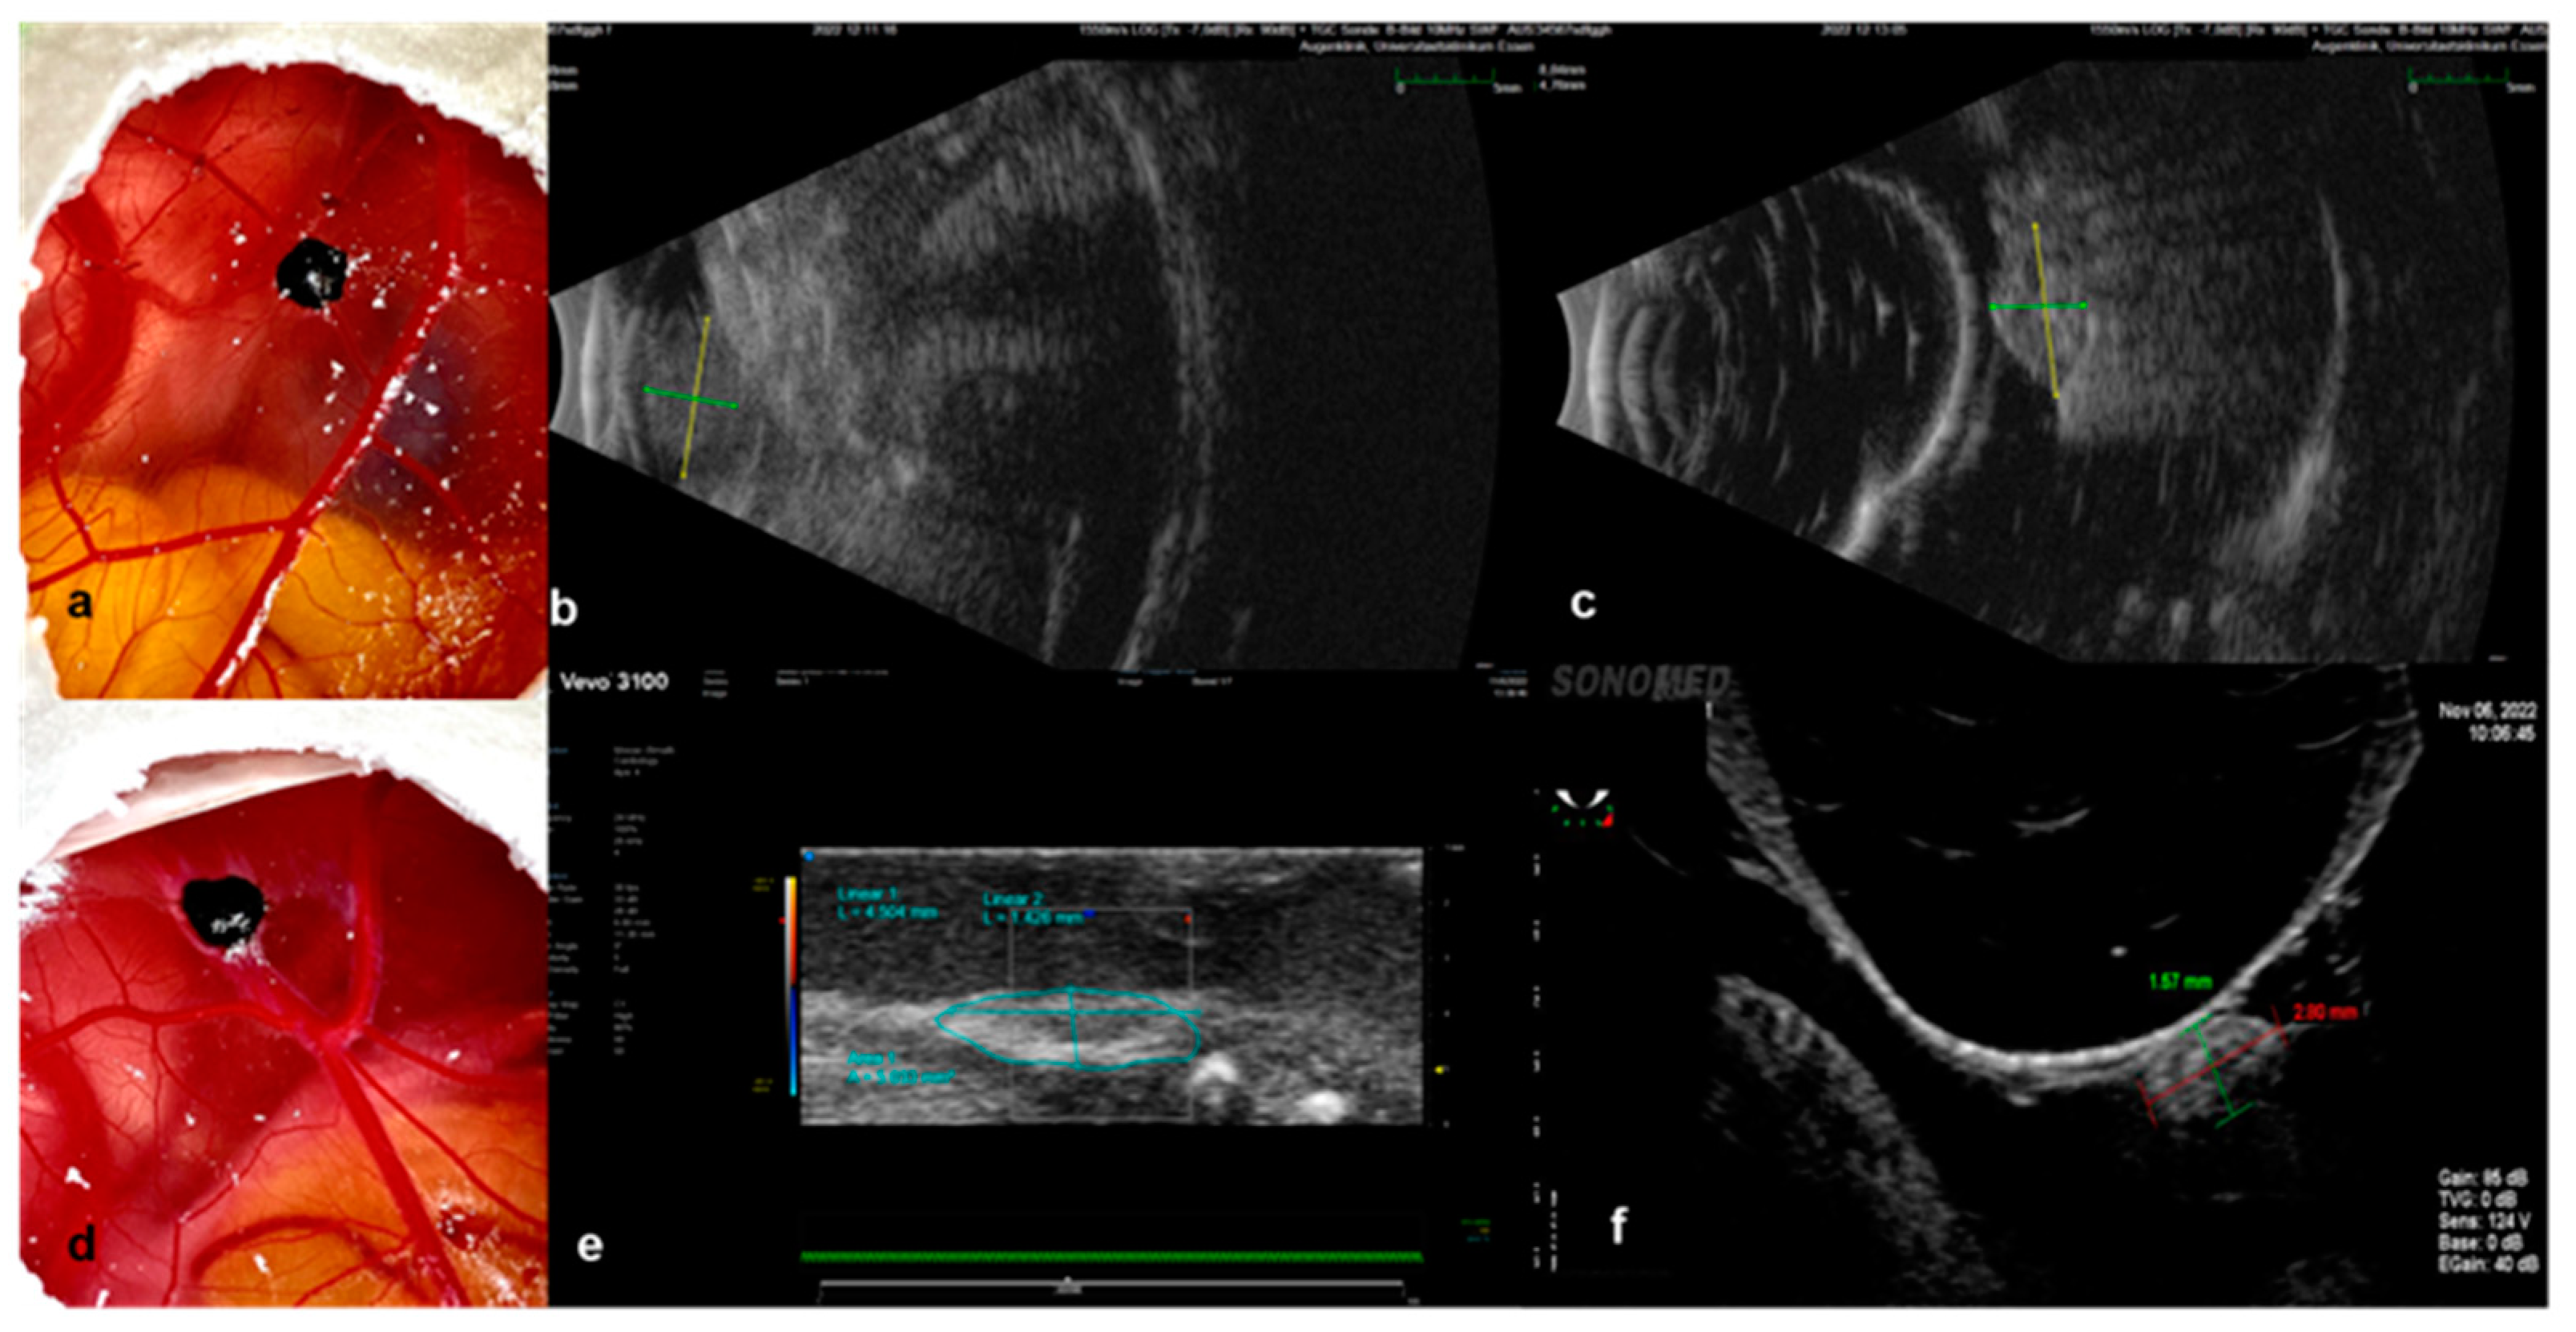

2.4.1. Ultrasound

3.2.1. Ultrasound